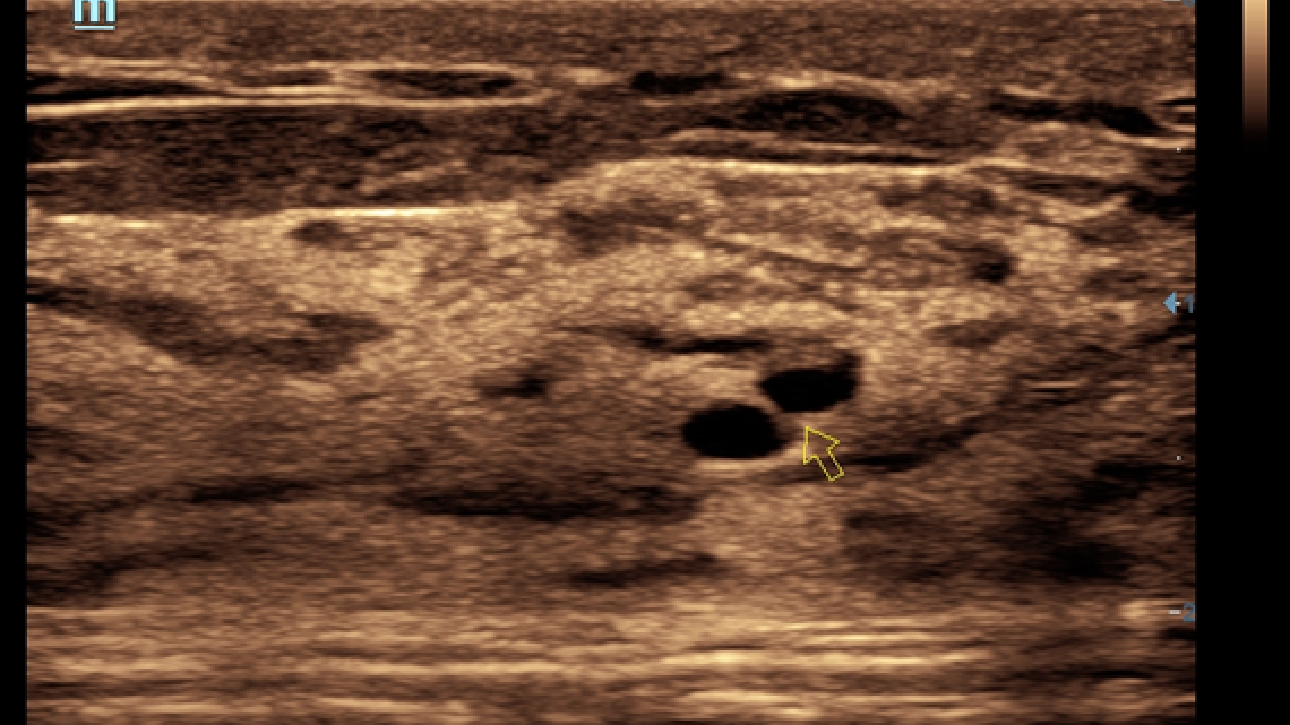

X-Insight es la soluci├│n intuitiva para una mejor visualizaci├│n.

La nueva soluci├│n de Mindray es una excelente transformaci├│n desde la continua comprensi├│n de las necesidades cl├Łnicas del usuario, combinada con la evoluci├│n de la tecnolog├Ła de los ultrasonidos m├Īs puntera. Repleto de vitalidad, con el ├║nico objetivo de visualizar el futuro y evitar los l├Łmites, el ec├│grafo DC-60Exp con X-Insight est├Ī constantemente mejorando con una escalabilidad aumentada. Como un socio personal, el equipo de ultrasonidos DC-60 Exp con X-Insight se centra en lo que verdaderamente importa, ayudando al usuario a administrar su pr├Īctica cl├Łnica con facilidad y seguridad.

Bas├Īndose en una profunda comprensi├│n de las necesidades del usuario, el sistema de ultrasonidos DC-60 Exp con X-Insight est├Ī dise?ado para ofrecer una alta eficiencia con im├Īgenes de precisi├│n, la cual se ve potenciada por una claridad inmediata, una inteligencia excepcional y benefici├Īndose de una c├│moda experiencia.